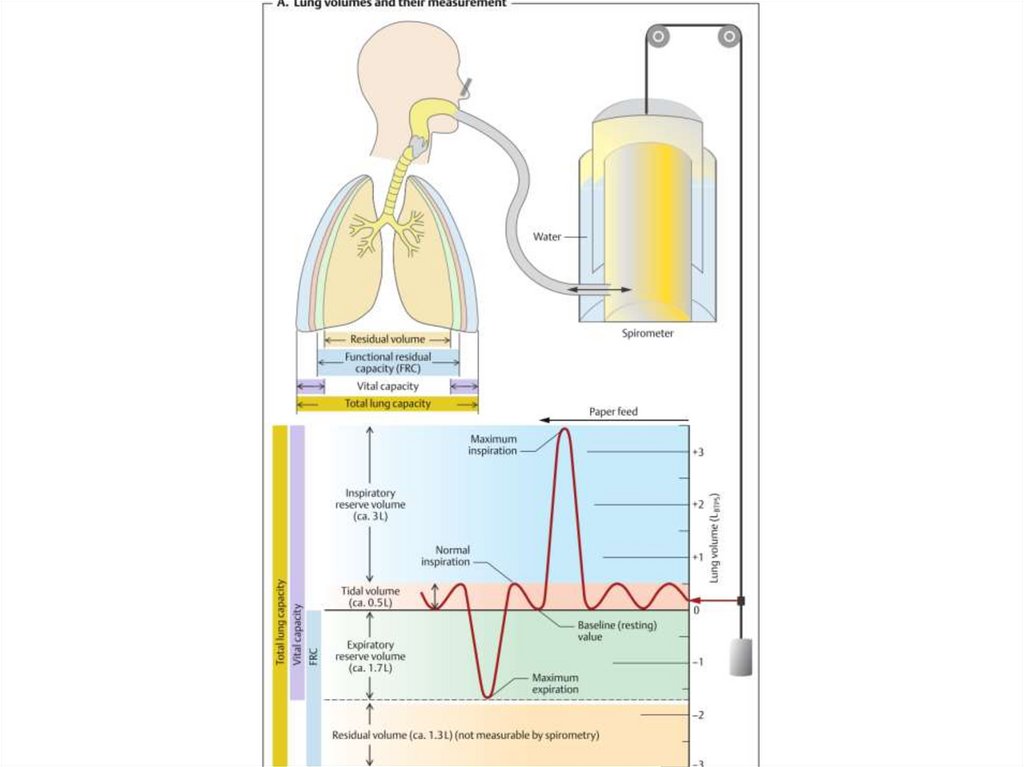

Схемы дыхания: Пневмоторакс на изображениях